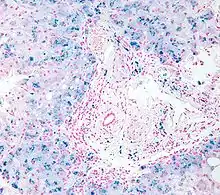

Micrograph of liver biopsy showing iron deposits due to haemosiderosis. Iron stain.

Histopathology of the liver, showing Kupffer cells with significant hemosiderin deposition (shown next to a hepatocyte with lipofuscin pigment, which is a common normal finding). H&E stain.

Prussian blue iron staining, highlighting the hemosiderin pigment as blue. This finding indicates mesenchymal iron overload (within Kupffer cells and/or portal macrophages) rather than parenchymal iron overload (within hepatocytes).[40]